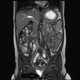

Dilated bladder

Urinary retention is an inability to completely empty the bladder. Onset can be sudden or gradual. [Source: Wikipedia ]